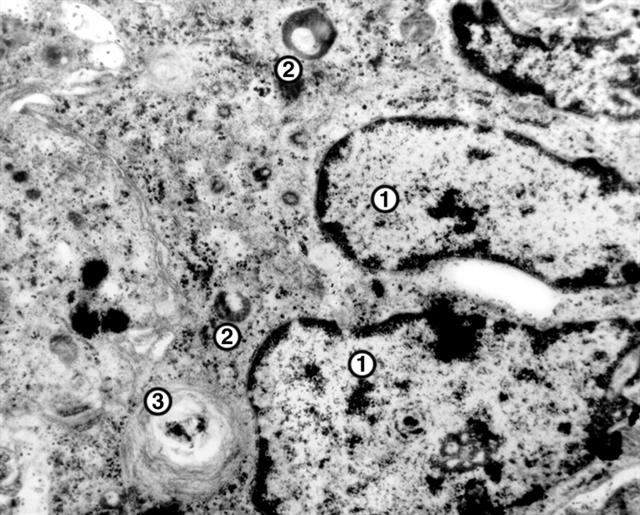

Рис. 1. Электронограмма участка гигантской многоядерной клетки инородных тел: 1 — ядра, входящие в состав одной клетки; 2 — лизосомы; 3 — фагосомы; ´15000.